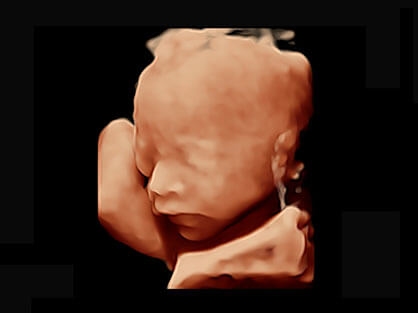

作为P系列家族成员之一,P40 Plus采用银河集团官网高端超声系统平台——极光,并以时尚秀丽、小巧灵动的外观设计绽放出灵动之韵、科技之美。高端平台的使用保证了P40 Plus优质的基础图像;完备的高级功能可满足您全身应用的基本需求;丰富的探头配置、多样的高级4D成像及分析软件为您日益增多的妇产应用需求提供丰富的诊疗方案。

可同时显示组织结构表面和内部的轮廓信息,达到透视效果,为临床提供更丰富的诊断信息。

宽频带腹部凸阵探头和腹部容积探头、大角度腔内探头和腔内容积探头、独特的生殖专用曲柄探头,为妇产应用提供全面诊疗方案。